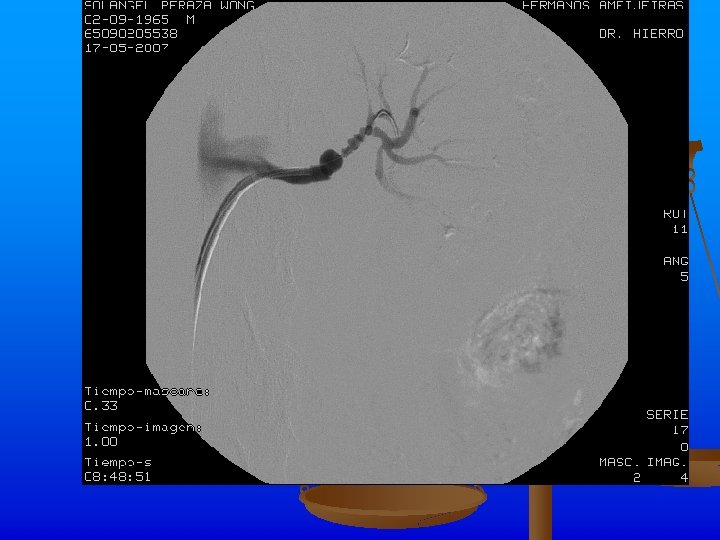

Exámenes Complementarios n n n Rx de tórax: Ligeros signos de hiperinsuflaciòn pulmonar. ICT normal. Índice de presiones de MI dentro de límites normales. Angio TAC: Se realiza angio. TAC abdominal inyectándose 120 ml de contraste, apreciándose áreas de estenosis y dilatación de ambas arterias renales, con un patrón arrosariado y zonas de hipoperfusión corticales en los polos de ambos riñones. Hay buena eliminación y concentración renal bilateral.

Se realiza angiplastia transluminar percutànea de arteria renal izquierda y se coloca stent de 18 X 4 mm con la administración de 1000 Uds. de heparina y la administración de contraste sin complicaciones